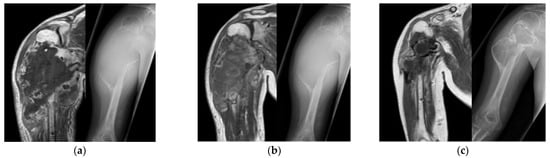

Four patients (57.1%) were assessed as having a stable disease during this period based on images; thus, they underwent ADM/MTX front-load therapy (Figure 3, patient No. 2). Due to the progression of the primary lesion, one patient (14.2%) was changed to the CDDP-based regimen.

Figure 3.

Representative case 2. The patient (patient No. 2) was referred to our hospital due to swelling of right shoulder. Based on the biopsy results, the patient was diagnosed with conventional osteosarcoma. The radiography at the initial visit (a). After induction of window therapy with CBDCA + IFO, the size of the tumor did not change (b). Thus, ADM/MTX was administered before surgery (ADM/MTX front-load). After several additional cycles of chemotherapy, the tumor responded to chemotherapy (c); however, an amputation was recommended due to the invasion of the neurovascular bundles. After surgery, the patient completed the mOS-91 regimen, and there is currently no evidence of disease. ADM, Adriamycin; CBDCA, carboplatin; IFO, ifosfamide; mOS-91, modified OS-91; MTX, methotrexate.